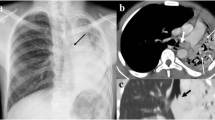

CT angiography of a pulmonary sequestration in a 6-year-old boy who was asymptomatic, but had a persistent dense image in the left pulmonary base. a Axial CT image. A large vessel is seen arising from the aorta, with multiple branches supplying a pulmonary mass. b Anterioposterior maximum intensity projection image. Three systemic vessels coming from the aorta are seen to feed the pulmonary sequestration. c Posteroanterior shaded surface display (SSD) image. The 3D depth perception created by SSD technique improves recognition of spatial relationships of the three vessels arising from the aorta. Two veins are also shown in the upper area of the image. With a cine-loop rotating image, the origin and the course of vessels can be better depicted

CT angiography is relatively new, and possibly one of the most important applications of helical CT (Choo et al. 2006; Lawrence 2008; Marini et al. 2009; Poole and Ferguson 2010; Chung et al. 2010; Khandelwal et al. 2011). CT angiography provides high-quality vascular imaging, and can depict congenital and acquired vascular abnormalities of the chest in children. Standardized CT angiography and arterial timing bolus test (or bolus-tracking technique) protocols are recommended in such cases (Table 3). Optimal contrast enhancement is best achieved using a power injector, which should be used whenever possible. With CT angiography, one can analyze vascular abnormalities of the pulmonary arteries, aortic arch and great vessels (double aortic arch, pulmonary sling, etc.) (Figs. 1, 8, 9, 10, 11) (Katz et al. 1995; Ghersin et al. 2005; Turner et al. 2005), pulmonary vein anomalies (Fig. 19) (Ou et al. 2009; Vyas et al. 2012), cardiac and coronary lesions (Fig. 20) (Saad et al. 2009; Goo et al. 2009; Lapierre et al. 2010; Siripornpitak et al. 2011), cardiac surgery postoperative status (Marini et al. 2009), and vascular lesions (Khandelwal et al. 2011). Furthermore, it is useful for studying congenital lung malformations (pulmonary sequestration, congenital cystic pulmonary airway malformation) (Biyyam et al. 2010), in which depiction of the systemic (aortic feeding) vessel is important for establishing the definitive diagnosis (Garcia-Peña et al. 2013) (Figs. 2, 3, 12, 13, 14).